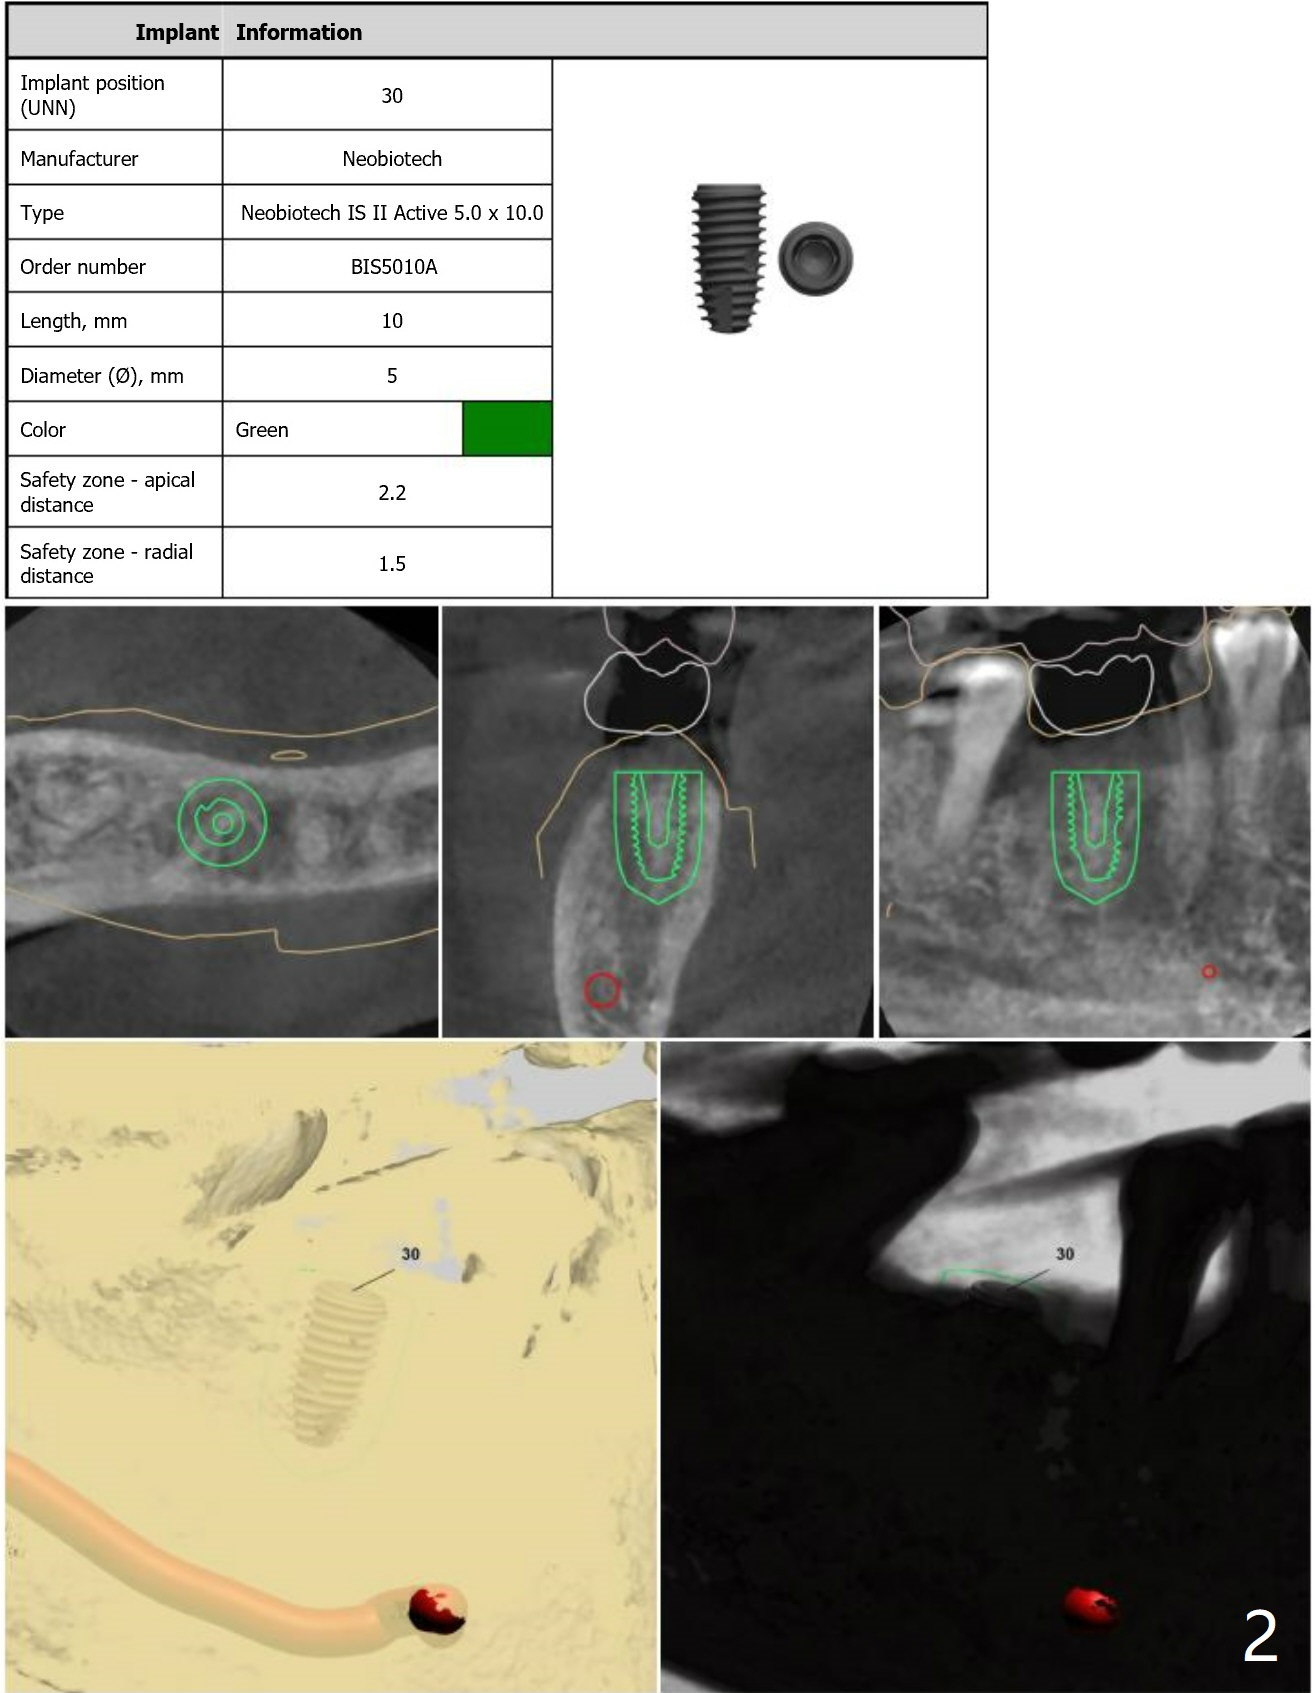

Guide Made Out of 5x5 cm Scan

Three months post socket preservation, the 60-year-od male patient returns for guided surgery at #30. Since the guide is made out of 5x5 cm CT scan, it may be not stable. Also do not expect high torque. Use cortical tap cautiously.